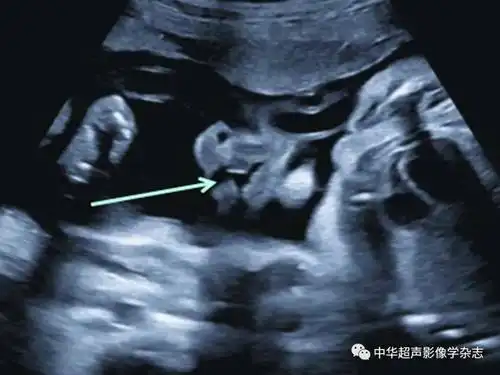

在妊娠20~24周超声检查时,应通过观察鼻唇冠状面判断上唇是否有唇裂

胎儿:颅盖完全或部分缺如,全前脑,无脑,颜面结构缺如,无眼,小眼,唇裂